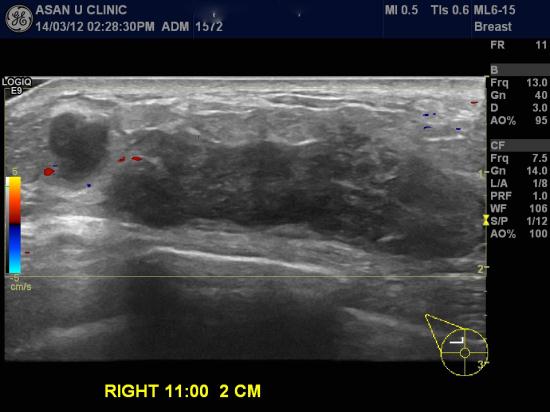

59세 여성으로 건강검진상 이상소견으로 내원한 분입니다.

오른쪽 유두에서 1CM거리부터 바깥쪽으로 길게 연결되어

가장긴길이가 5CM의 초음파 프루브에 잡히지 않을 정도였습니다.

중심핵생검으로 조직검사실시하고 동측 겨드랑이에 비대된 4개정도의 전이의심소견을

흡인세포검사하고....

유방의 침윤성 소엽암과 림프절 전이로 진단되셨습니다.